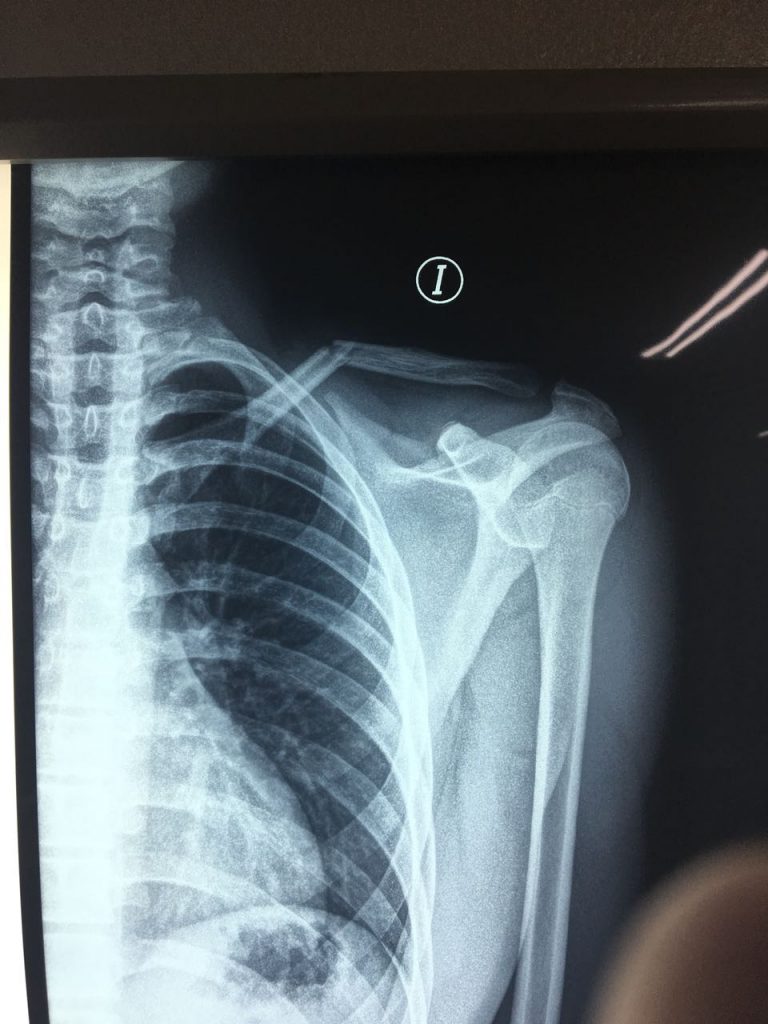

Following my accident during a soccer tournament in March, I went to a local hospital where my shoulder was immobilized in the ER. After a few days, the shoulder still hurt a lot. My pediatrician suggested to contact Laura Porcella, who is the Ambassador for HSS in the Dominican Republic. After speaking with her, coincidentally, Dr. David Helfet was in the DR, so we sent her a picture of my x-ray for him to take a look at. Immediately, he informed us we should set up an appointment next Monday at his office at HSS.